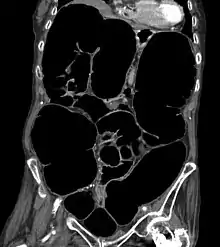

CT-Scan showing a coronal section of the abdomen of an elderly lady with an IPO.